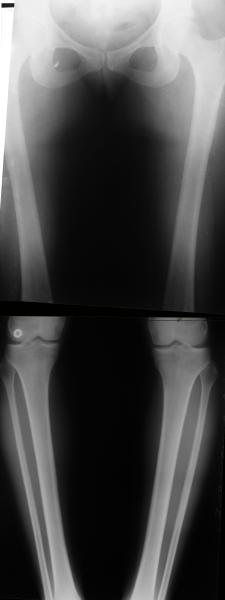

Re: Деформация голеней

Alexander Chelnokov 13 Сентябрь 2005, 23:23

Операция была интересной, много полезного опыта приобрел.

Снимки в приложении - фас сравнительный с неоперированной ногой. Жду критики.

Впрос про остеотомию большеберцовой непраздный. Эта получилась при надломе несколько более наклонно, чем я делал (сейчас проблема,

как на второй ноге сделать так же). Вот этот высоящий "зуб" центрального отломка не заменит ли в плане косметики то, что получается при медиализации дистального?

Отправитель: T. Derek V. Cooke 14 Сентябрь 2005, 18:23

|

Hi Alex:

Nice job!

It is very interesting to me that as you have derotated the tibia you have centred the patella, I think and the prox tibia looks much more anatomic.

The analysis in the attached images is direct, just using the tools.

Tibial tilt is perhaps more than you want but the tibial correction is to 90 (very slight over

correction.

Will need full length views to tell us about the hka but it appears neutral.

Measurements took 4 mins

Derek